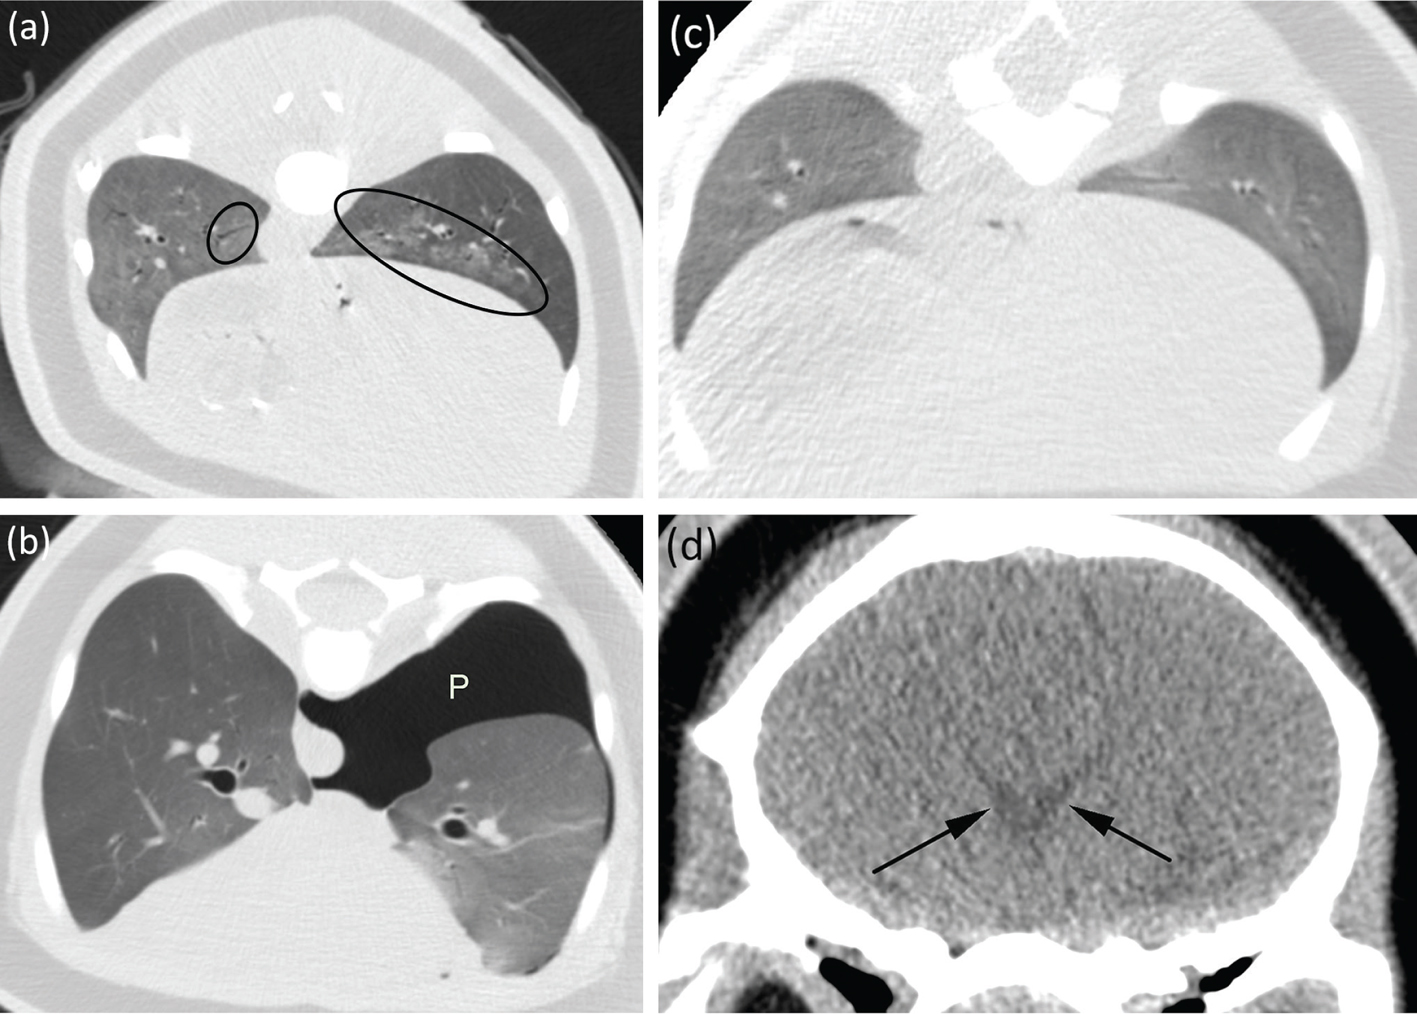

A CT scan on 12 October 2017 revealed peribronchial infiltrates suggestive of aspiration pneumonia (Fig. 7a), granular material within the gastrointestinal tract potentially due to sand ingestion during stranding, and intracranial ventriculomegaly indicating mild hydrocephalus (Fig. 7d). His behaviour and respiratory rate (Fig. 3) changed significantly on 17 October 2017, when his pattern of actively swimming, diving and interacting with staff switched to having increased buoyancy, spending more time logging at the surface, less time interacting with caretakers and breathing more rapidly. These changes, initially attributed to gastrointestinal distress, were likely due to pneumothorax. This was not diagnosed until his second CT scan on 16 November 2017, which revealed a left-sided pneumothorax without evidence of tension (Fig. 7b), resolution of the previous pneumonia and improved but not resolved intracranial ventriculomegaly. Over time, clinical progress was observed as buoyancy decreased, respirations normalized and the pneumothorax spontaneously resolved, as demonstrated in the third CT scan (3 January 2018), which revealed (Fig. 7c) no evidence of pneumothorax or pneumonia as well as resolution of the intracranial ventriculomegaly.

Fig 7

Fig. 7 Select CT scans of stranded beluga calf (Delphinapterus leucas) DL1705 (the patient’s left side is on the right side of the images): (a) peribronchial infiltrates (indicated by ovals) on 12 October 2017; (b) left-sided pneumothorax (P) on 16 November 2017; (c) resolved pneumonia and pneumothorax on 3 January 2018; (d) mild hydrocephalus (indicated by arrows) in the lateral ventricles seen on the initial scan of DL1705’s head, taken on 12 October 2017; the condition improved and finally resolved on subsequent scans.